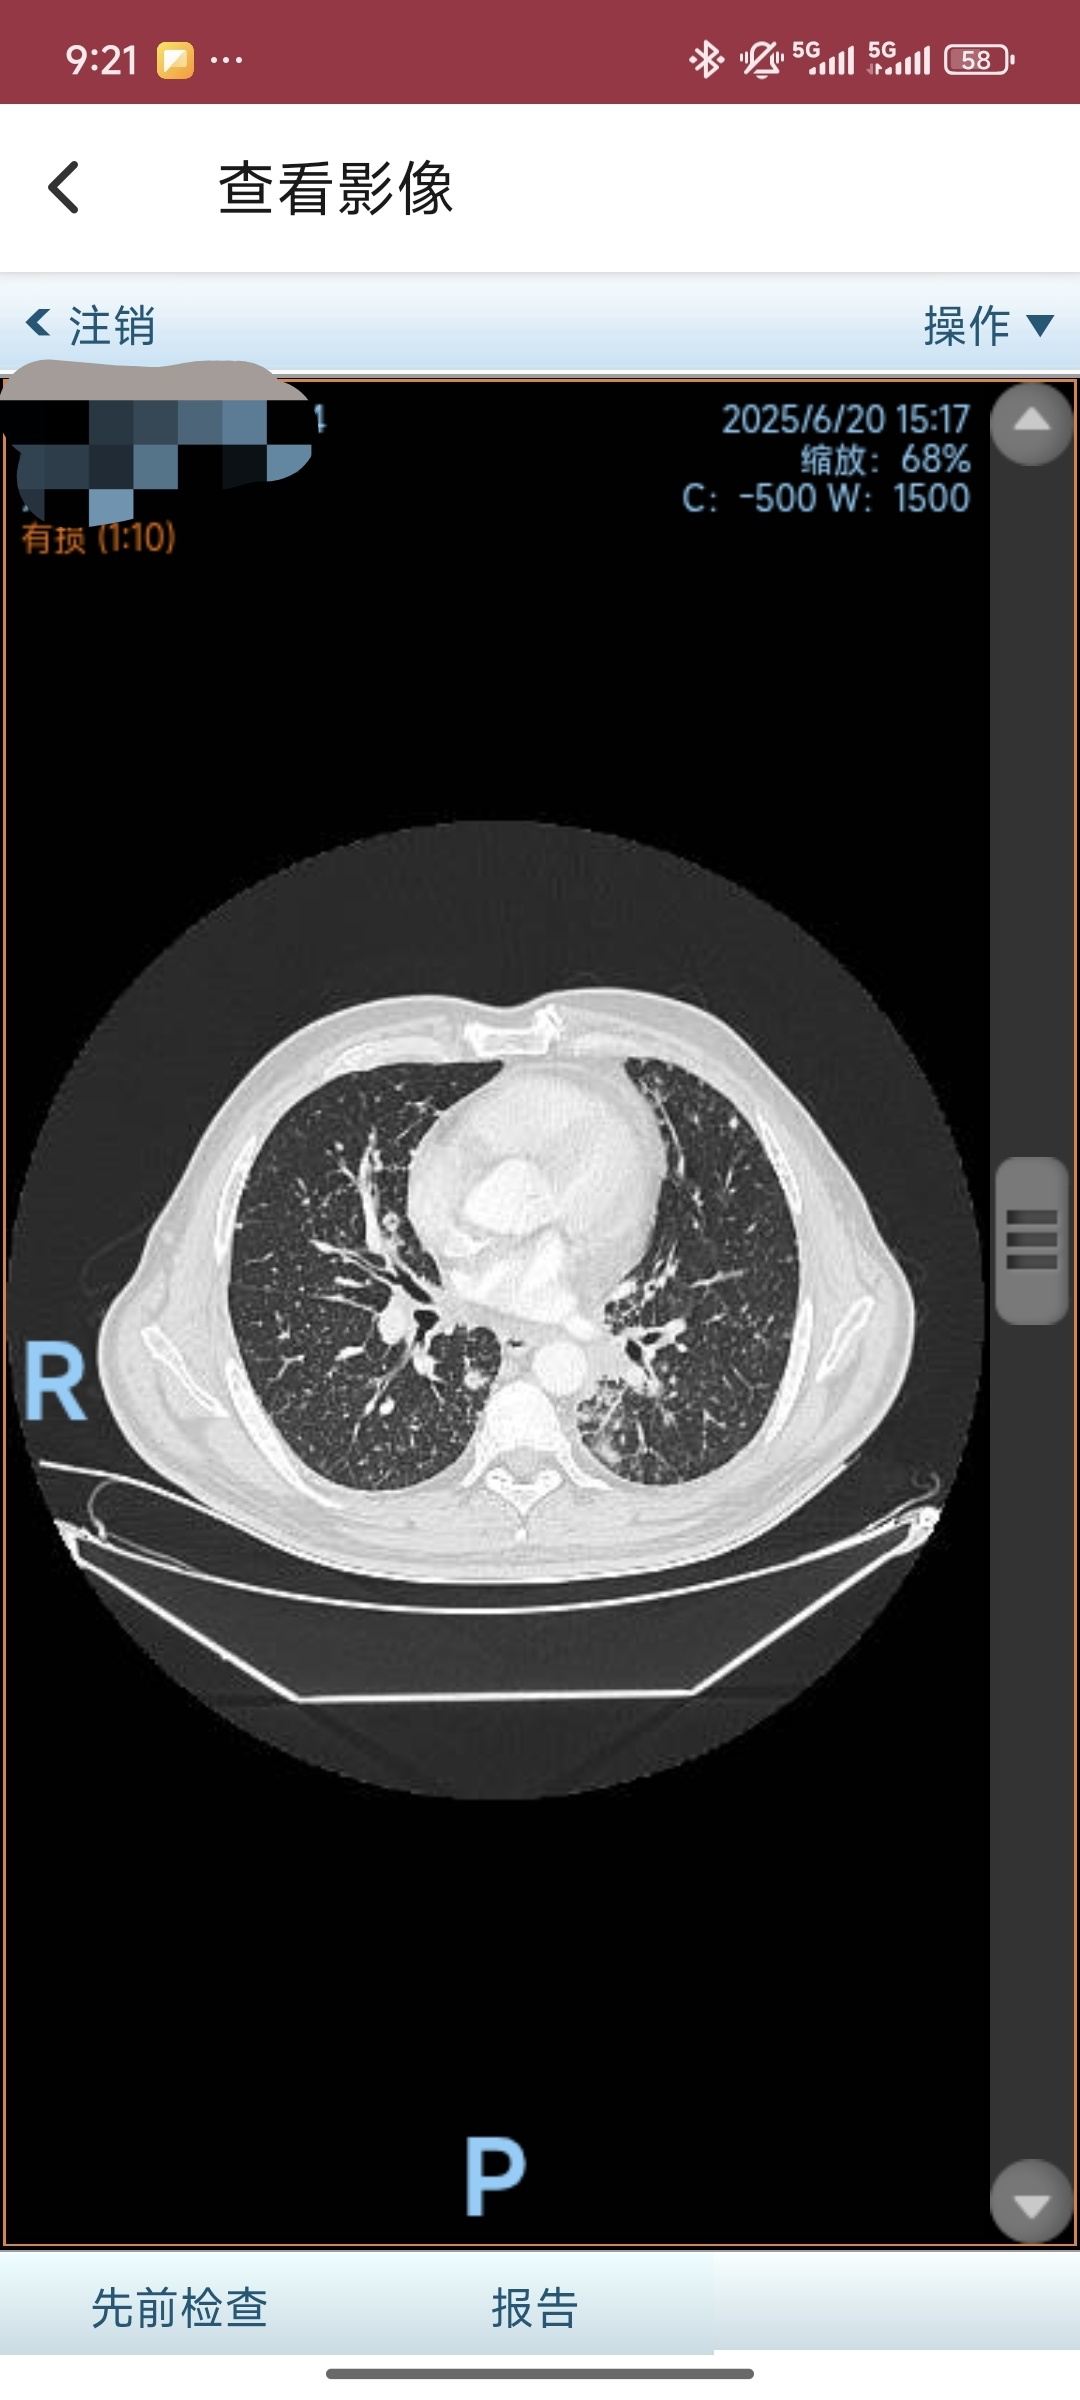

2025-06-19 本院PET-CT:左肺下叶肺门旁肿物,符合肺癌疗后表现;伴远端阻塞性炎症;双肺弥漫多发结节伴轻度代谢,考虑转移;右肺下叶癌性淋巴管炎可能大。右颈部、双锁骨区、左侧胸肌间、纵隔及双肺门多发淋巴结伴高代谢,考虑转移可能大;双颈部另见淋巴结伴轻度代谢,性质待定。肝S4高代谢灶,考虑转移。骨多发高代谢灶,考虑转移;左股骨头高密度结节,未见高代谢,请对比疗前影像。